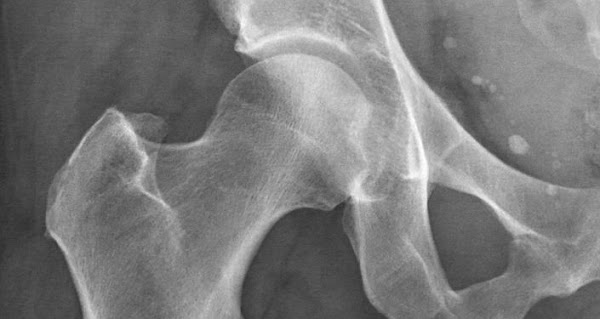

Di chứng đó là ‘hoại tử vô khuẩn chỏm xương đùi (AVN) hay còn gọi là c.hết tế bào xương. Có ít nhất 19 trường hợp đã gặp phải tình trạng này sau khi mắc nCoV, vừa được phát hiện tại một bệnh viện ở thành phố Mumbai của Ấn Độ.

Nói về căn bệnh lạ này, bác sỹ Sanjay Agarwala – người đứng đầu Bệnh viện Hinduja ở Mumbai, bang Maharashtra cho biết: “AVN là bệnh c.hết tế bào xương cục bộ do tổn thương tại chỗ, có thể do tác dụng phụ của thuốc hoặc do bệnh tật. Đây là tình trạng nghiêm trọng do các khu vực xương bị c.hết tế bào sẽ không thể hoạt động bình thường được, chúng bị yếu dần đi và có thể sẽ vỡ”.

Khu vực dễ bị AVN nhất chính là phần hông, tiếp đến là đầu gối, vai, mắt cá chân, khuỷu tay và cổ tay.